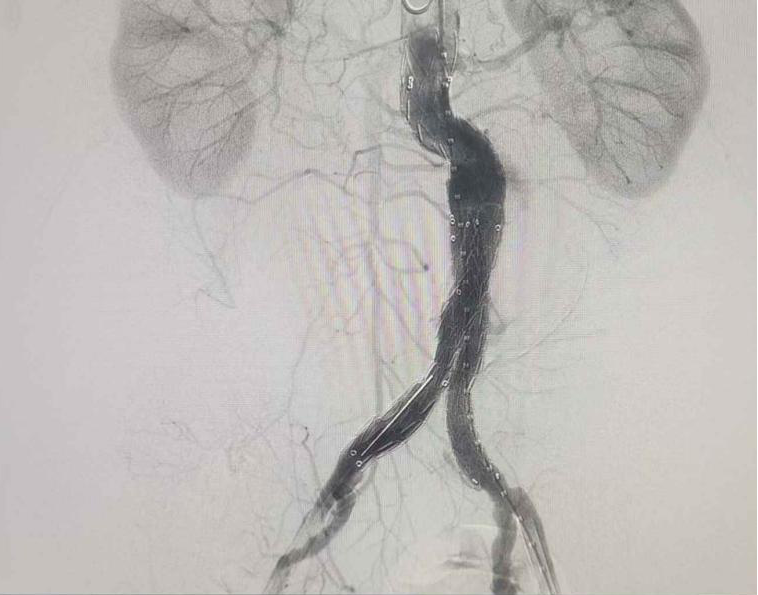

(術(shù)中造影)

經(jīng)科室血管外科團隊詳細(xì)研判病情、術(shù)前MDT討論,并與患者家屬充分溝通,決定為患者實施“腹主動脈覆膜支架腔內(nèi)隔絕術(shù)”。普外一科(肝膽胰外科)血管外科團隊在中國科學(xué)技術(shù)大學(xué)附屬第一醫(yī)院血管外科專家指導(dǎo)下,與麻醉科、導(dǎo)管室等科室密切協(xié)作,術(shù)中采用股動脈穿刺入路,結(jié)合三維血管重建與數(shù)字減影血管造影(DSA)動態(tài)導(dǎo)航,成功完成腹主動脈-髂動脈覆膜支架置入術(shù)。

這場高難度的微創(chuàng)介入手術(shù)僅耗時1個小時便順利結(jié)束,術(shù)中造影顯示隔絕腹主動脈瘤的腹膜支架位置精準(zhǔn),成功保留了老人雙側(cè)腎動脈及髂內(nèi)動脈,最大程度保障了重要臟器的血流供應(yīng)和生理功能。在科室醫(yī)護團隊精心照護下,患者術(shù)后第5天康復(fù)出院。